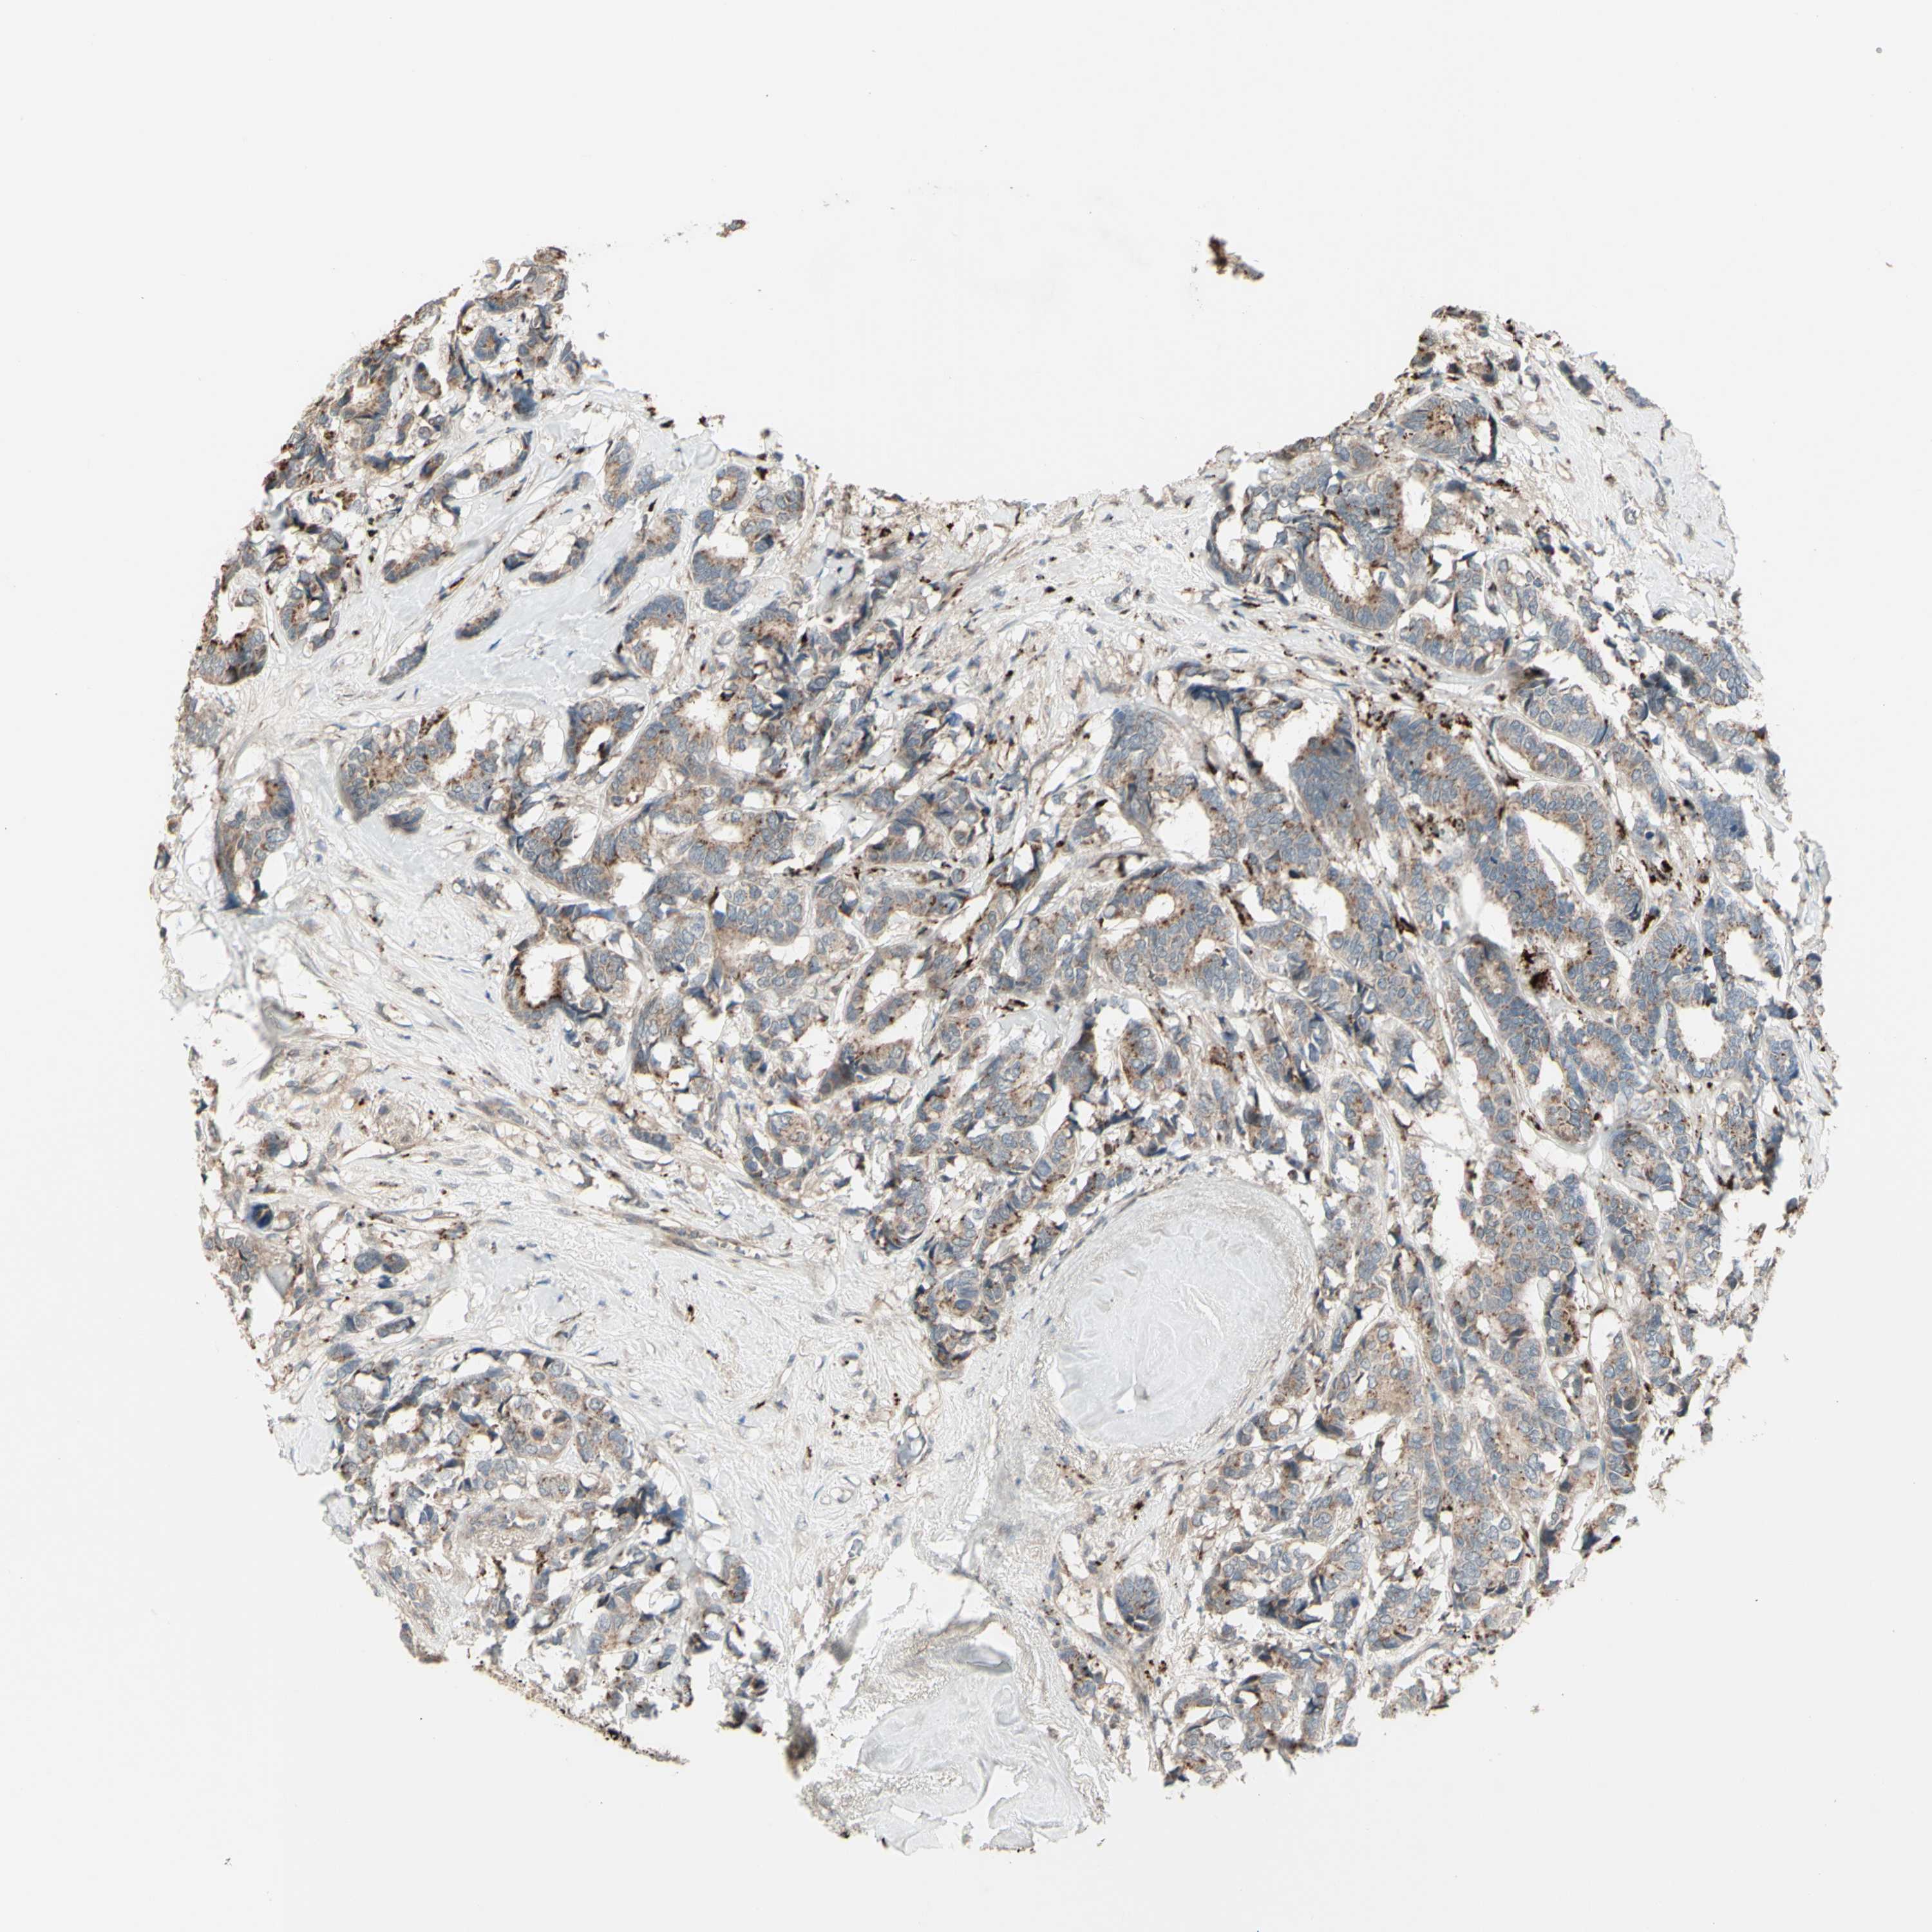

CANCER BREAST CANCER Show tissue menu

BRCA TCGA BRCA VALIDATION PROTEIN EXPRESSION